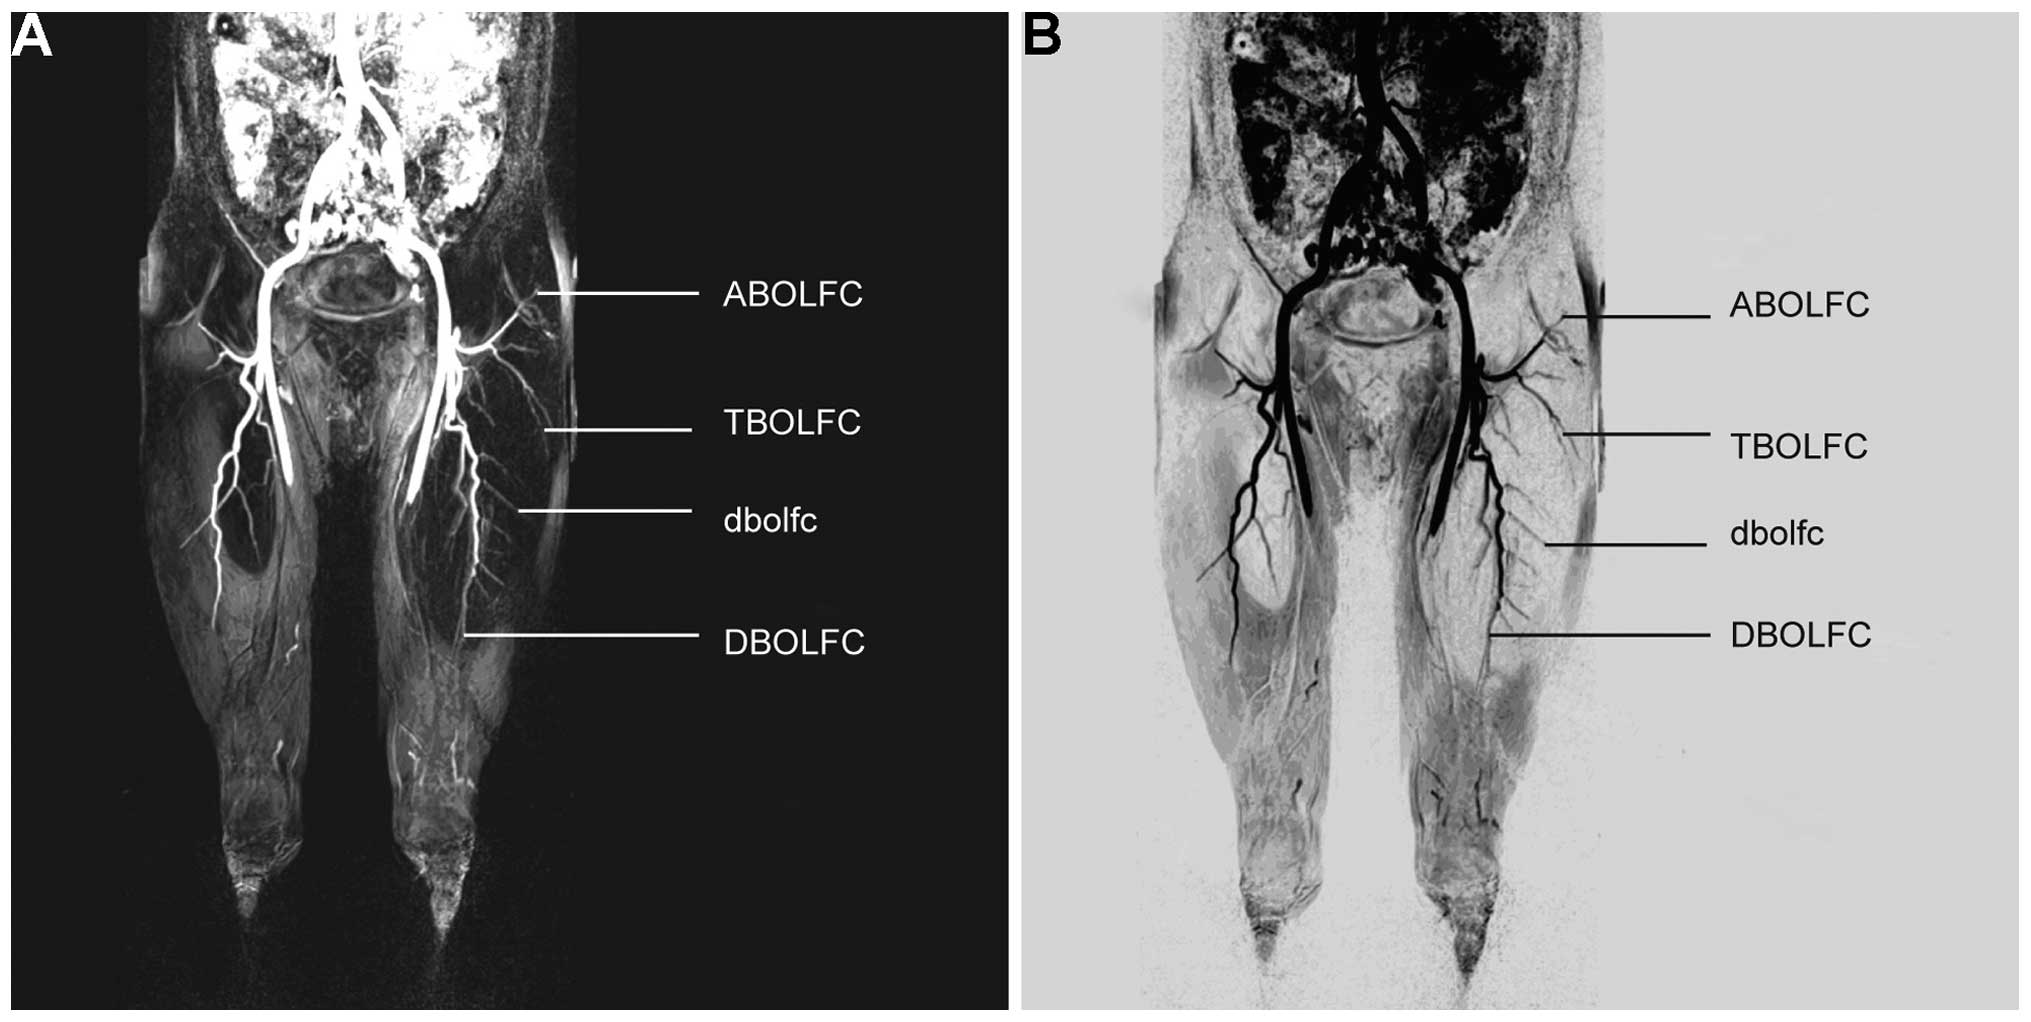

As shown in Table I, the LFCAs of the bilateral lower limbs were well visualized by 3D-CE-MRA in all 68 patients. The anatomical pattern of the LFCA was type Ia in 80 cases (58.8%), type Ib in 21 cases (15.4%), type II in 20 cases (14.7%), type III in 3 cases (2.2%) and type IV in 12 cases (8.8%). Tertiary vascular trees (primary, main trunk of LFCA; secondary, ascending, transverse and descending branches; tertiary, muscular perforating vessels) were identified in 94 limbs (69.1%). The intermuscular orientation of the perforating vessels was also clearly shown with MRA. The length of the descending branch vascular pedicle (the linear distance from the origin of the branch to the distal end) ranged from 41 to 323 mm. As shown in Fig. 1A and B, the left LFCA (type Ia) originated from the left DFA and subsequently trifurcated into the ascending, transverse and descending branches. As shown in Fig. 2A and B, the right LFCA (type Ib) originated variably from the right DFA and subsequently trifurcated into the ascending, transverse and descending branches. As shown in Fig. 3A and B, the descending branches of the bilateral femoral circumflex arteries converged with the ascending branch of the bilateral superior genicular arteries. Type Ib LFCA, i.e. an LFCA originating variably from the FA, was identified in 21 cases. Among these cases, TS-MIP reconstruction of the opening portion of femoral artery revealed the specific origin of the LFCA to be from the anterolateral part of the FA in 10 cases and from the posterolateral part of the FA in 11 cases, and another from the inferior part of the DFA in 19 cases.

Figure 2.

Type Ib LFCA. (A) Three dimensional-contrast-enhanced magnetic resonance angiography reconstructed maximum intensity projection and (B) digital subtraction angiography images showed that the LFCA originated variably from the femoral artery and subsequently trifurcated into the ascending, transverse and descending branches. LFCA, lateral femoral circumflex artery; ABOLFC, ascending branch of the LFCA; TBOLFC, transverse branch of the LFCA; DBOLFC, descending branch of the LFCA; dblofc, perforating branch of the LFCA.